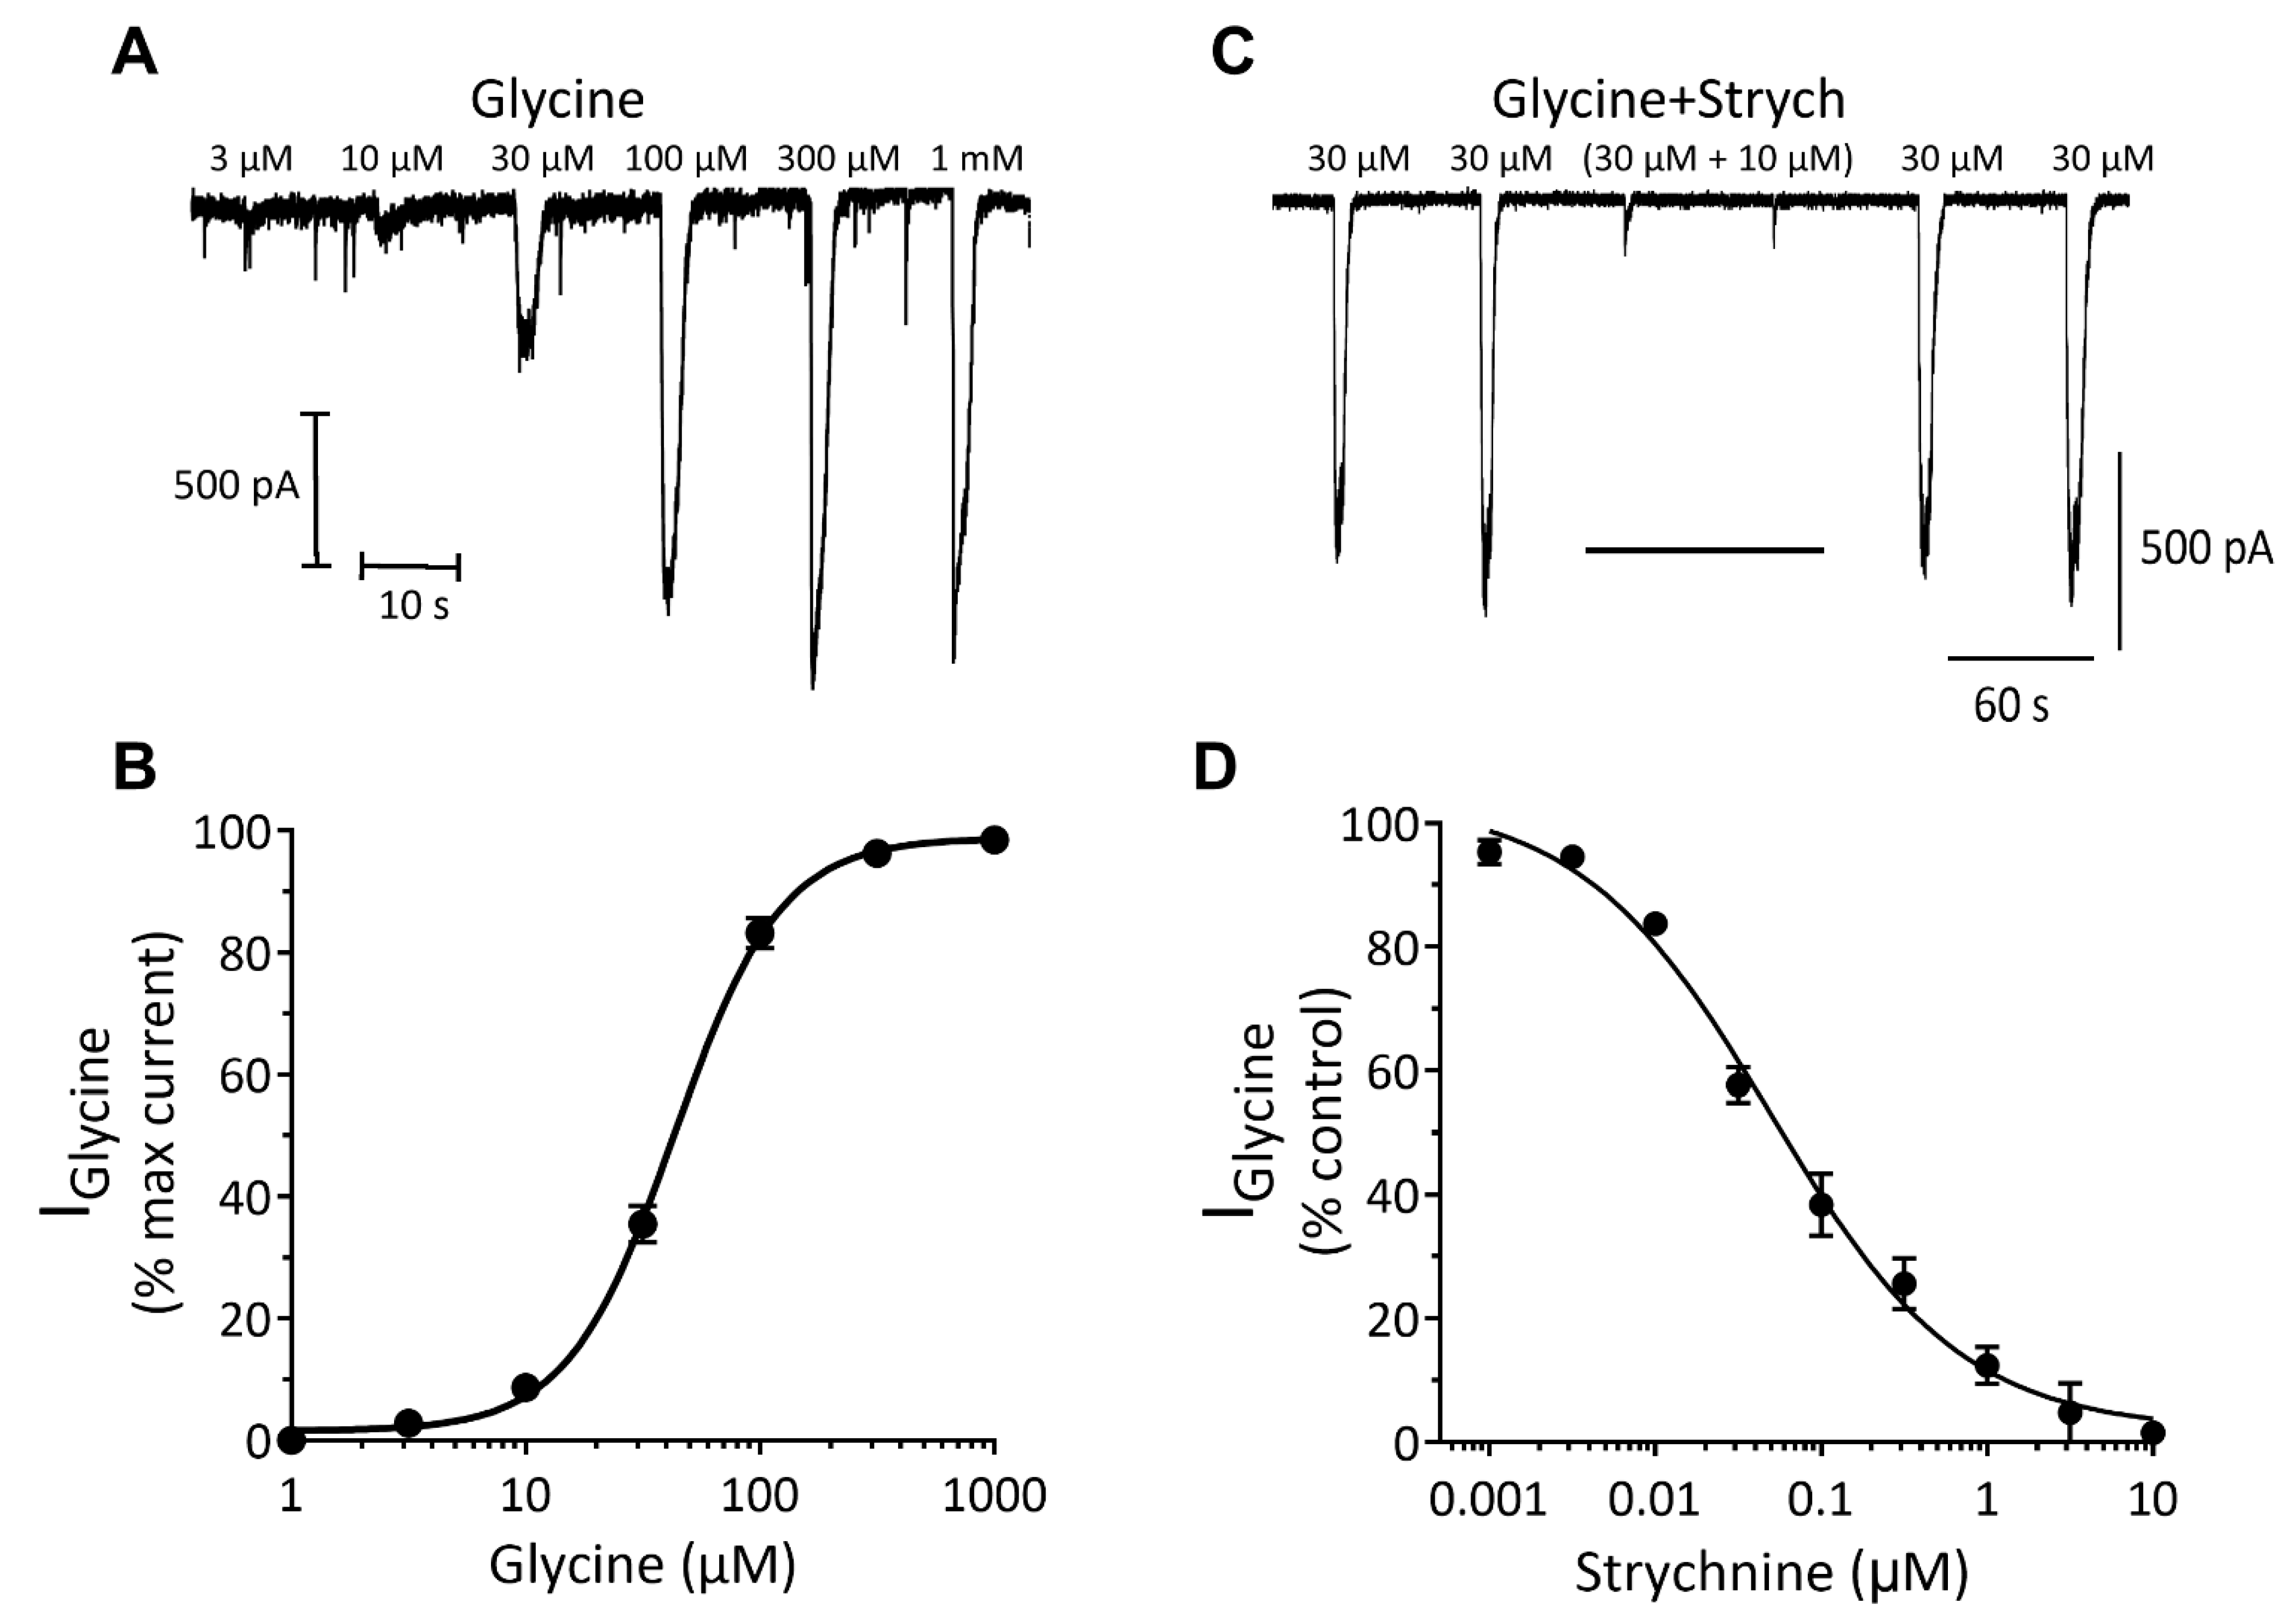

Inhibitory Ligand-Gated Currents